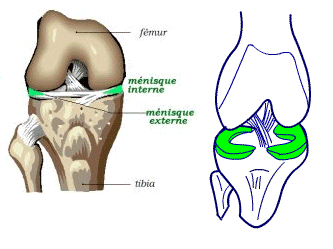

Les ménisques sont des fibro-cartilages interposés de chaque côté des compartiments interne et externe du genou. En forme de croissant ou de quartier de pomme, ils sont solidement attachés en périphérie à l'enveloppe capsulaire et à leurs extrémités antérieure et postérieure au centre du tibia (Figure 1).

En coupe transversale, les ménisques ont une forme triangulaire avec une pér iphérie plus large et bien vascularisée (zone rouge) et un bord libre plus mince et non vascularisé (zone blanche).

Figure 1 : anatomie des ménisques (à gauche) et vascularisation périphérique sur une coupe transversale (à droite)